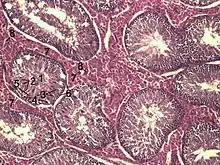

Coupe d'un testicule de porc : les cellules de Leydig (7), sont entre les tubes séminifères (1 à 6) et en contact avec les capillaires sanguins (8) pour y déverser la testostérone.

- (Histologie) Les cellules glandulaires qui occupent les interstices entre les tubes séminifères des testicules et qui sécrètent de la testostérone et de l'androstènedione.